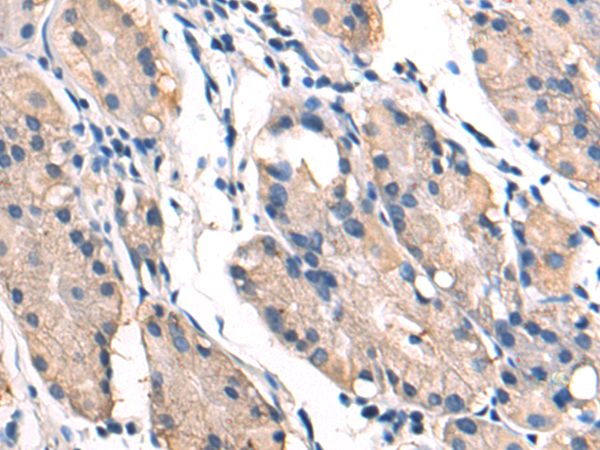

分类: 科研抗体货号: P04340别名: MEMD; CD166应用: WB,IHC反应种属: Human, Mouse, Rat